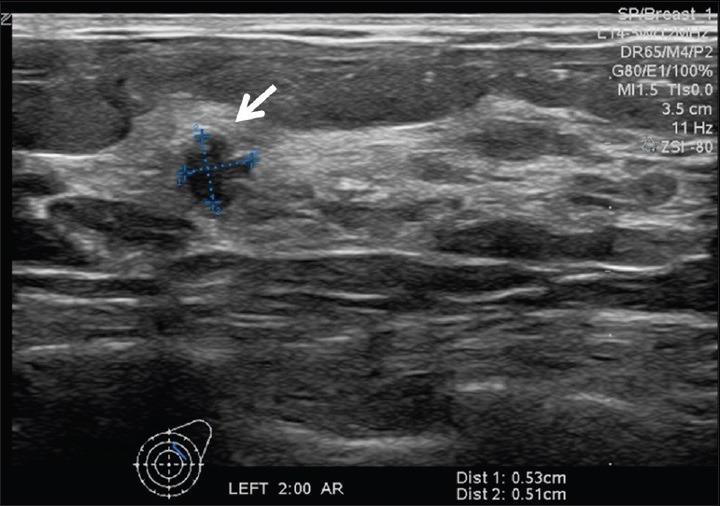

Metastatic tumors are rare in the breast. Well-differentiated neuroendocrine tumors (WDNETs) are slow-growing neoplasms that arise from neuroendocrine cells, particularly in the gastrointestinal tract and bronchial tree. Metastatic WDNET to the breast is a rare entity. We present a case report of ileal WDNET metastatic to the breast which was initially identified as a small mass in the patient's left breast on screening mammography. Targeted ultrasound identified a suspicious mass, and ultrasound-guided percutaneous core biopsy was performed. Pathology revealed metastatic WDNET. Breast magnetic resonance imaging (MRI) was then performed and demonstrated left axillary Level 2 lymphadenopathy, and liver lesions were suspicious for metastasis. The patient underwent abdominal computed tomography (CT) to evaluate for distant metastatic disease. A spiculated mass was found near the ileocecal valve, suggestive of primary ileal WDNET. In addition, CT identified multiple liver lesions, most compatible with metastasis. Indium 111 OctreoScan confirmed radiotracer uptake in the ileum consistent with primary neuroendocrine tumor. In this report, we review the imaging characteristics of metastatic WDNET to the breast by different imaging modalities including mammogram, ultrasound, and breast MRI.

转移性肿瘤在乳腺中较为罕见。高分化神经内分泌肿瘤(WDNETs)是起源于神经内分泌细胞的生长缓慢的肿瘤,尤其多见于胃肠道和支气管树。乳腺转移性WDNET是一种罕见的情况。我们报告一例回肠WDNET转移至乳腺的病例,该病例最初在乳腺钼靶筛查时被发现为患者左乳的一个小肿块。靶向超声检查发现一个可疑肿块,并进行了超声引导下经皮穿刺活检。病理结果显示为转移性WDNET。随后进行了乳腺磁共振成像(MRI)检查,结果显示左侧腋窝2级淋巴结肿大,肝脏病变可疑为转移灶。患者接受了腹部计算机断层扫描(CT)以评估远处转移情况。在回盲瓣附近发现一个有毛刺的肿块,提示原发性回肠WDNET。此外,CT检查发现多个肝脏病变,最符合转移表现。铟111奥曲肽扫描证实回肠有放射性示踪剂摄取,与原发性神经内分泌肿瘤一致。在本报告中,我们通过不同的成像方式,包括乳腺钼靶、超声和乳腺MRI,回顾了乳腺转移性WDNET的影像学特征。